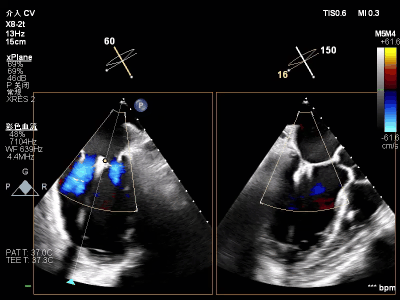

【术前超声心动图提示】

室性功能性二尖瓣反流(混合性MR),重度(MR 5+),反流位于2区–3区,左室射血分数低(EF27%)

【瓣膜与功能特点】

前超声评估明确关键指标:二尖瓣瓣环呈扩张状态(前后径约3.3cm,瓣环面积约4.75cm²,前叶长约2.1 cm,后叶长约1.4 cm),瓣叶增厚且后叶栓系明显,前后叶对合不良;同时伴左房、左室明显扩大,左室收缩功能显著减低,合并节段性运动异常。经团队综合评估,该患者为“多支冠脉支架植入后+低射血分数+重度功能性二尖瓣反流(混合性MR)”的高危病例,左室射血分数(EF)仅20%,在接受GDMT药物优化治疗6周后EF值提升至27%,但症状仍无法有效缓解,遂决定为其实施经心尖入路二尖瓣缘对缘修复术(TA-TEER)。

【术中操作(含关键步骤超声)】

鉴于患者术前心功能差、多支架植入的特殊情况,手术全程需兼顾“精准操作”与“保护心功能”双重要求:在全麻与经食道超声的协同引导下,团队先突破心功能受损导致的术野稳定性难题,稳步经心尖建立手术轨道与输送鞘;随后聚焦二尖瓣2偏3区精准置入一枚Ⅱf型夹合器,成功攻占这一解剖位置深、毗邻结构敏感、容错率极低而操作难度陡增的区域。